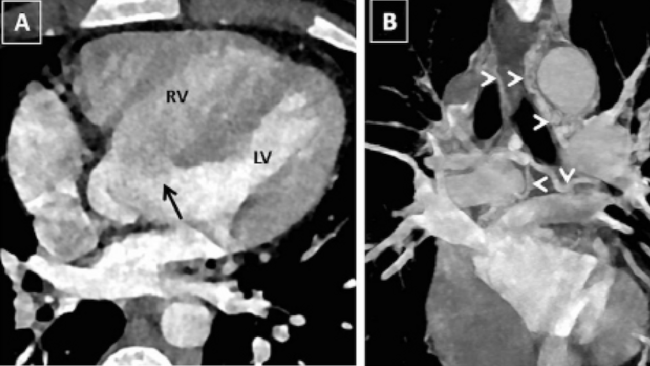

A 19-year-old male presented with history of cyanosis noted since early childhood, dyspnea, and angina on exertion New York Heart Association class II for the past 3 years. Physical examination revealed central cyanosis, pan digital grade 3 clubbing, saturation of 74%, and a grade 3 ejection systolic murmur in the left 3rd intercostal area. Echocardiography showed a large non restrictive ventricular septal defect with severe pulmonary stenosis and aortic override, suggestive of tetralogy of Fallot (TOF). Computed tomography (CT) angiography confirmed the diagnosis of TOF and showed the presence of multiple aortopulmonary collaterals (APCs) arising from bilateral subclavian arteries, coronaries, and aorta with presence of dual left anterior descending artery (LAD) with dominant LAD from the right coronary artery (RCA) (Figure 1). CT angiography nicely depicted the type 3 APCs arising from both the coronaries supplying bilateral lungs with delineation of dual LAD (Figure 2 and Video 1). Pulmonary arteries were well developed. The patient is planned for intracardiac repair of TOF along with surgical ligation of the APCs.